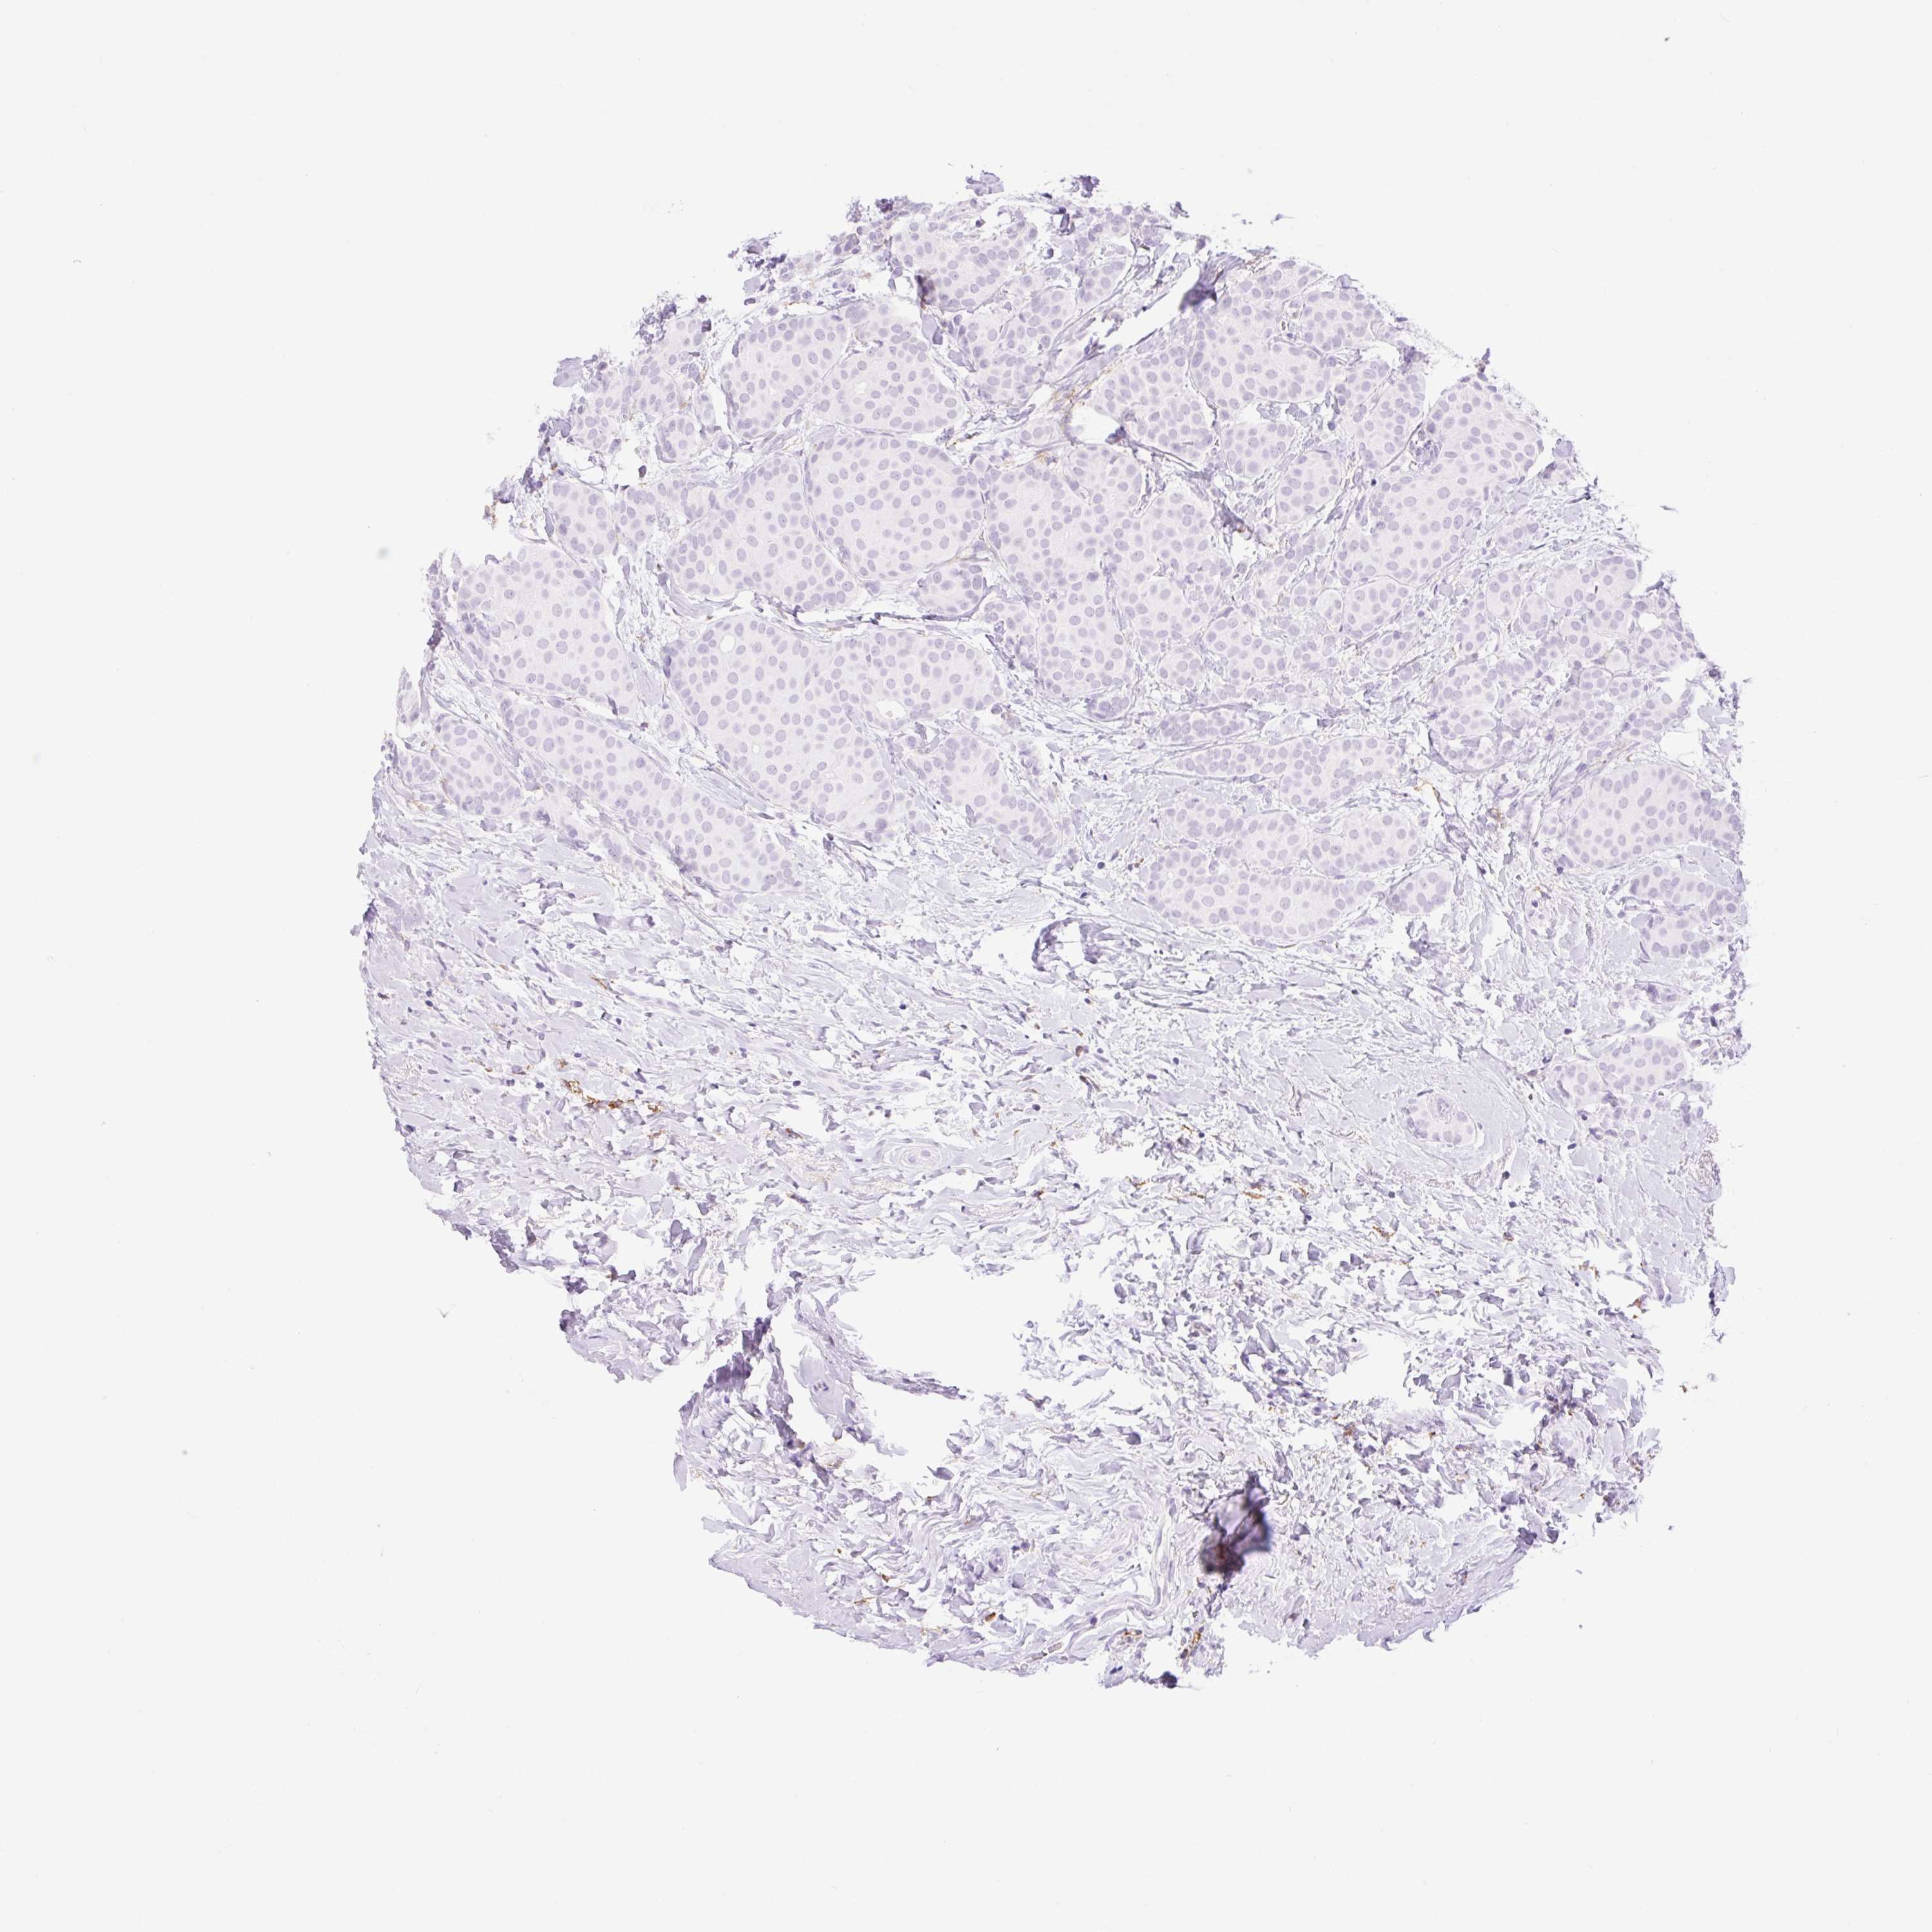

CANCER BREAST CANCER Show tissue menu

BRCA TCGA BRCA VALIDATION PROTEIN EXPRESSION